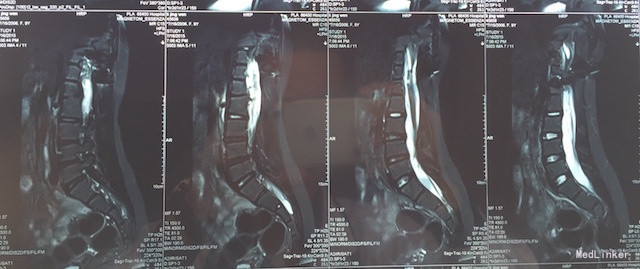

查体:四肢感觉、肌力及肌张力无明显异常,直腿高抬试验(-),双侧足背动脉搏动良好,腰椎活动可,病理征(-)。 辅助检查:胸腰椎MRI(如下图):脊髓下段受牵拉平对第3腰椎下缘,合并脊柱旁占位及脊柱裂可能。

诊断:脊髓栓系综合征 治疗:脊髓栓系松解术

随访与讨论:手术顺利,术后神经受牵拉症状需至少半年才能恢复。诊断及鉴别诊断:脊髓栓系综合征:是由多种脊髓先天性发育异常导致的系列临床综合征。脊髓下段因各种原因受制于椎管终末端,使其位置低于正常。根据该患者临床表现及影像学检查,考虑可能性大。马尾综合征:大多是由于各种先天性或后性原因之腰椎管绝对或相对狭窄,压迫马尾神经而产生一系列神经功能障碍,可有会阴区感染异常及大小便失禁,根据该患者影像学检查。